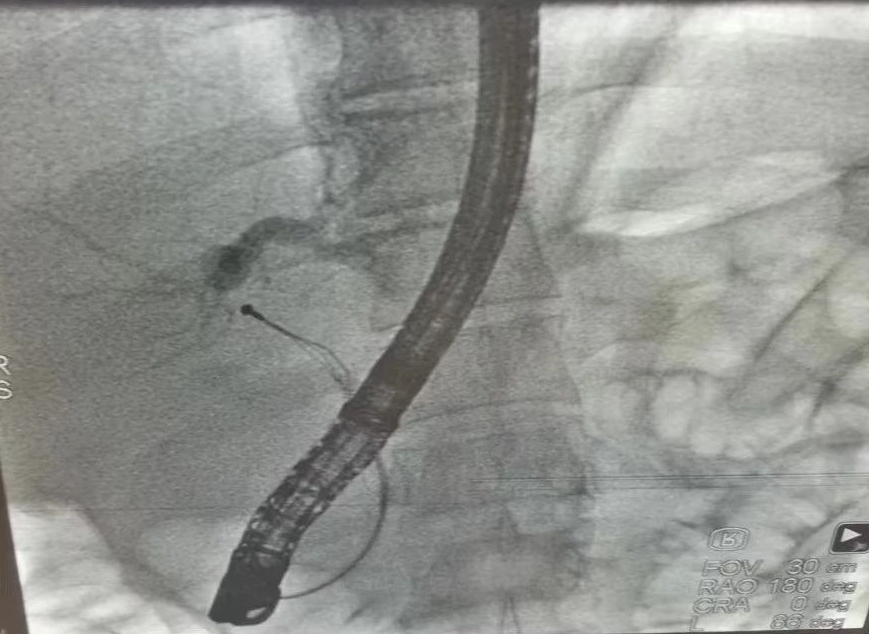

消化内科邱春雷主任与陈敬成副主任医师会诊后,与普外科张旭华主任、黄无浪主治医师及患者家属协商决定:为患者实行局麻内镜下逆行胰胆管造影(ERCP)+十二指肠乳头肌切开(EST)取石术+鼻胆管引流术(ENBD)。患者手术顺利,术中胆总管可见多个直径约0.6cm结石及胆泥,解除了胆总管梗阻,术后患者康复良好,腹痛、腹胀等症状缓解。

专家解说:ERCP作为一项高新技术,属国家四级手术范畴,是内镜专家公认的技术难度高、操作复杂的内镜技术,被誉为内镜技术“皇冠上的明珠”。(文图:陈敬成 审核:邱春雷 周臻 彭晓露)